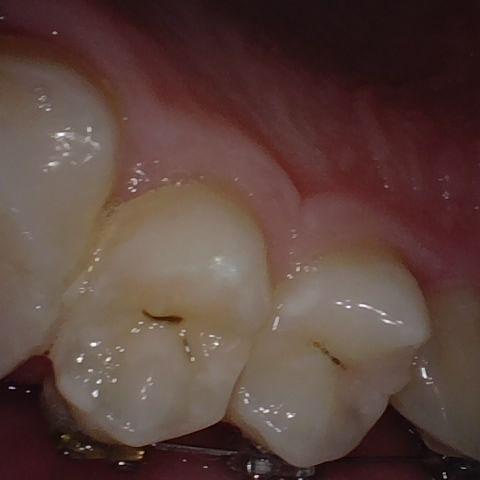

Annotated as "Good"